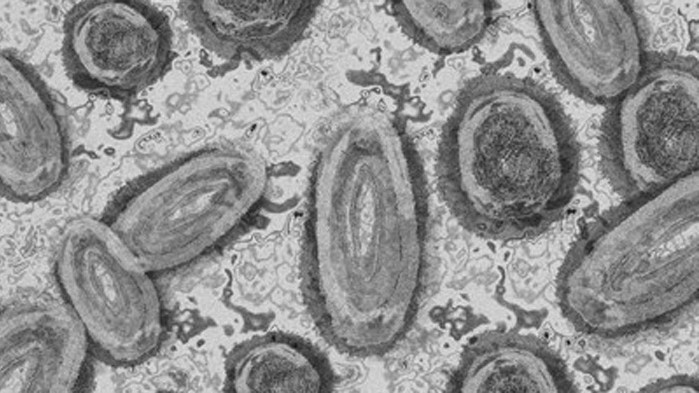

Двама души, които са били в контакт с вируса, причиняващ маймунската шарка, са били имунизирани във Франция, съобщи ДПА.

Маймунската шарка към този момент е записана в 20 страни, заяви наскоро Световната здравна организация. Във Франция има седем доказани случая на маймунска шарка, разгласи здравната министърка Брижит Бургиньон, която съобщи, че обстановката със болестта е под надзор.

Във Англия пък, където бяха открити повече случаи на болест с маймунската шарка, над 1000 души бяха имунизирани с препарата " Имванекс ". Страната закупи над 20 000 дози от него, написа Българска телеграфна агенция.

В Германия няма известия за имунизации, само че здравните управляващи поръчаха до 40 000 дози от имунизацията.